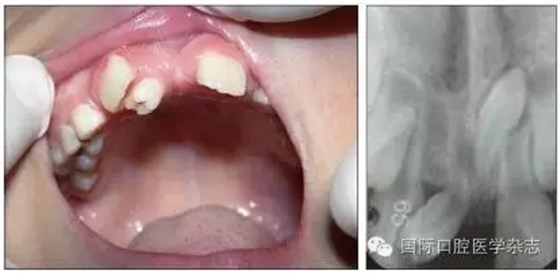

個別牙先天缺失常常造成牙列異常間隙,多數牙先天缺失會影響咀嚼功能和牙列形態(tài),嚴重者影響面容和美觀。牙齒的形態(tài)異常,如融合牙等會使牙弓大小、形態(tài)及咬合關系發(fā)生異常。乳牙滯留是指繼承恒牙已經萌出,未能按時脫落的乳牙。乳牙牙根未吸收或非典型性吸收可導致恒牙萌出方向改變、位置異常,常見于下頜乳中切牙滯留,恒中切牙于舌側出齦,呈現“雙排牙”現象(圖5)。上頜牙齒在滯留乳牙腭側出齦則可能形成反(圖6)。

左:口內照;右:X線片。

圖5 上頜前牙區(qū)多生牙導致上頜中切牙間隙,右上中切牙扭轉

Fig 5 Supernumerary teethin the area of maxillary anterior teeth caused incisor gap, reversed rightupper incisor

圖6 右上乳中切牙遲脫引起右上中切牙腭向異位萌出

Fig 6 Late exfoliation ofright upper primary incisor caused ectopicpalatal eruption of right upper incisor

牙齒異位萌出是指恒牙在萌出過程中,未在牙列的正常位置萌出,兒童口腔臨床最常見的是上頜第一恒磨牙和上頜尖牙的異位萌出。造成第一恒磨牙異位萌出的原因包括:第二乳磨牙和第一恒磨牙的牙冠體積較大;頜骨的發(fā)育不足,尤其是上頜結節(jié)發(fā)育不足;第一恒磨牙的萌出角度異常,牙軸向近中傾斜等,歸根結底是在第一恒磨牙萌出階段出現了牙量和骨量不調的問題,頜骨發(fā)育不足是最主要的原因。發(fā)生率為2%~6%,男性多于女性,其中2/3發(fā)生在上頜,可單側或雙側對稱出現。第一恒磨牙的異位萌出常常造成第二乳磨牙早失,牙弓長度減小。臨床上,常用分牙簧分離第一恒磨牙與第二乳磨牙,或使用恒磨牙面粘著舌扣的Halterman矯治器,或變異Nance弓推第一恒磨牙向遠中的方法,改變恒牙萌出道,阻斷恒磨牙對乳磨牙的壓迫吸收,引導恒磨牙正常萌出。圖7顯示為一左上第一恒磨牙異位萌出的患兒,左上第二乳磨牙松動,牙弓長度減少[6]。

左:口內照;右:全景片。

圖7 左上第一恒磨牙異位萌出,左上第二乳磨牙松動

Fig 7 Ectopic eruption ofleft upper the first permanent molar, loose of left upper the second primarymolar